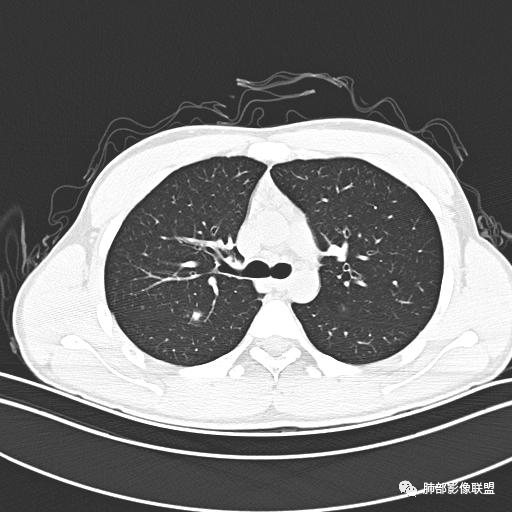

【每日晨读】年轻男性,发热+皮疹+肺内点晕

主  诉:发热、全身皮疹2天。

现病史:患者源于2天前受凉后出现发热,最高体温为38.5℃,且颜面部出现少量皮疹,无鼻塞、流涕、咳嗽、咳痰,未在意而未作特殊处理,次日全身皮疹逐渐增多至全身,伴轻度瘙痒,在当地卫生所给予抗病毒、抗感染治疗(具体用药不详)体温有所下降,但皮疹无明显消退,无腹痛、头痛,食欲无明显减退,为进一步诊治,遂于今日急来我院求治,患者目前精神尚可,体力正常,食欲正常,睡眠正常,体重无明显变化,大便正常,排尿正常。

小强:青年,发热,皮疹;双肺散在结节,周围磨玻璃,点晕征,疱疹病毒感染,鉴别荚膜组织胞浆菌,结核。 大雄:青年,急性起病,发热伴全身皮疹2天,抗病毒治疗体温有下降。双肺随机分布大小不等类圆结节,“点晕征”。考虑水痘-疱疹病毒(VZV)血播询问接触史,查体皮疹分布以及形态基本可诊断。 王开金江津中心医院呼吸科:青年男性,起病急,病程短,以发热,皮疹为首发症状,感染指标以单核细胞升高为主,胸部ct双肺多发结界,周围有晕,点晕表现,随机分布,同意於老师意见,水痘疱疹病毒血流感染累及肺。 王秀仙:双肺多发大小不等结节,周围有晕,边缘模糊,呈点晕征表现。青年,急性起病,发热伴全身皮疹2天,抗病毒治疗体温有下降。考虑疱疹病毒。鉴别荚膜组织胞浆菌。 傅昌瑜:19岁男性,发热、全身皮疹2天,单核细胞增高,双肺多发结节,结节边缘见边界不清磨玻璃影。点晕征+发热、全身皮疹+单核细胞增高——考虑水痘-带状疱疹病毒肺炎。 一切∮随缘:年轻男性,发热,皮疹两天,实验室,CRP,PCT增高,影像:双肺多发散在磨玻璃结节,边界欠清,大小不等,呈点晕征改变,以血管束周围分布为主,局部血管束略增粗,其它无明显改变,考虑:1:病毒性肺炎(水痘疱疹病毒?不知道皮肤有无改变)2:真菌(组织胞浆菌,血管侵袭性肺曲霉)3:GPA4:寄生虫(实验室没有看到嗜酸细胞增高) 赵山河:双肺散在结节,周围有晕,边缘模糊,呈点晕征表现。青年,急性起病,发热伴全身皮疹2天,抗病毒治疗体温有下降。考虑水痘—疱疹病毒感染。洪桥爱:青年男性,发热、皮疹2天,伴瘙痒,皮疹于面部首发,之后进展至全身,虽然没有对皮疹进行描述,但是从出疹时间及皮疹进展情况,伴瘙痒,应该就是个水痘患者;CT提示双肺随机分布结节影,部分结节伴有边界不清晕征,考虑水痘血播肺。 刘强:年轻男性,急性起病,皮疹,发热,抗感染治疗体温下降,说明有效。影像表现为散在点晕征,感染类疾病谱(疱疹病毒,真菌,结核),结合年龄,皮肤皮疹,考虑水痘-疱疹病毒性肺炎。 小兜:男性,19岁,发热皮疹两天,颜面部至全身,CRP,降钙素及单核增高。CT示双肺散在小结节,周围伴磨玻璃影,点晕征,考虑为水痘-带状疱疹病毒(varicella-zoster virus,VZV)肺炎 必有路:青年,皮疹+发热+“点晕征”→水痘-疱疹病毒(VZV) 许慧良:青年男性患者,发热、皮疹2天,体温最高38.5℃,第3天皮疹扩展至全身,伴瘙痒,胸部CT:双肺多发随机分布的小结节,结节周边见边界模糊的晕征,考虑水痘病毒感染流心明智:男,19,急性起病,发热伴全身皮疹2天。出疹顺序头→全身,抗病毒有效。胸部CT:两肺多发大小不等类圆形实性小结节影,随机分布,结节周围环绕GGO,边界模糊,呈点晕征。出疹特点是关键,未提示。考虑:血播病毒性肺炎,水痘-疱疹病毒?麻疹?鉴别荚膜组织胞浆菌、TB、血管炎、寄生虫等。 浪迹天涯:病灶多为5-10mm大小结节,结节周围可见磨玻璃样的晕环,常多发,可分布于肺内任何区域,考虑水痘—带状疱疹病肺炎如果短时间内有新的一个区域浸润,更加能说明,